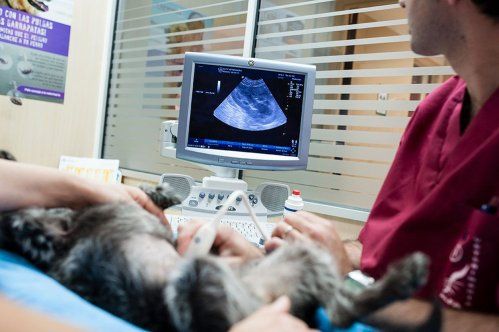

El uso de esta técnica de diagnóstico por imagen está muy extendido en la medicina veterinaria, dada su amplia variedad de aplicaciones: gestación, estudios cardíacos, problemas en la cavidad abdominal, consulta prequirúrgica...[...]